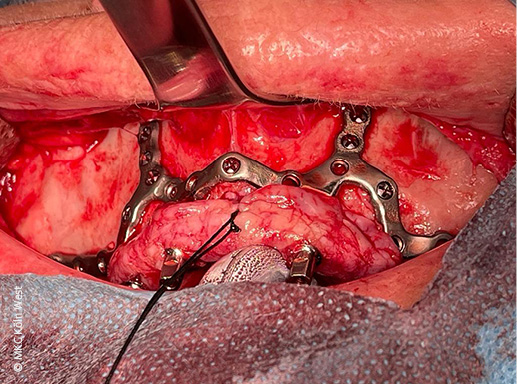

Über einen oberen vestibulären Bogenschnitt mit hoher marginaler Inzision wurde der Oberkiefer flächig subperiostal dargestellt (Freilegung der Apertura piriformis, beider Jochbein- bzw. Crista zygomaticus-Regionen sowie des atrophierten Alveolarkamms). Anhand der CAD/CAM-Bohrschablone wurden die vorgesehenen osteosynthetischen Schraubenkanäle in den tragfähigen knöchernen Strukturen des Viszerokraniums präpariert.

Anschließend wurde das einteilige Titan-Implantatgerüst inseriert und mit 1,5 mm-Titanschrauben (KLS Martin) an insgesamt vier Fixationspunkten stabil am Oberkiefer verschraubt (unter anderem paramaxillär und im Jochbeinbereich). Zur Austrittssicherung der vier Implantatpfeiler durch die Schleimhaut wurden gezielt kleine Stichinzisionen in der fixierten Gingiva angelegt.

Vor Wundverschluss erfolgte zur Optimierung der Weichgewebslager ein Bichat-Fettkörper-Verschiebelappen beidseits zur zusätzlichen Polsterung des Implantats (vestibuläre Abdeckung der Gerüstanteile). Die spannungsfreie mehrschichtige Wundadaptation konnte im Anschluss erreicht werden.